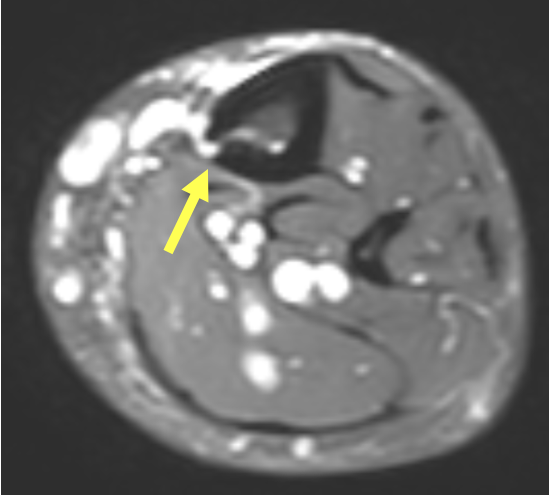

- Ausgeprägte Tenosynovitiden, v.a. der Flexorensehnen (Pfeile) (T1 FS KM)

- Synovitis der MCP D5, PIP und DIP Gelenke D5 (Pfeile) (T1 FS KM)

- Diffuses Weichteilödem entlang des 5. Strahles mit korrespondierender KM- Aufnahme (Pfeile) (T1 FS KM)